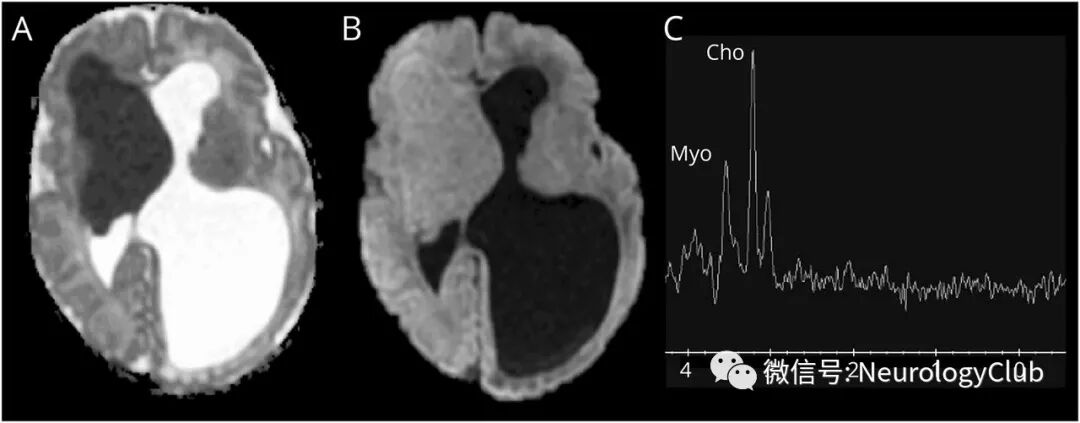

9天大女婴,在产前超声检查中发现脑部和心脏病灶,怀疑结节性硬化症。本例患者头颅MRI可见以Monro孔(孟氏孔)为中心的一巨大的脑室内和脑实质内肿块,有不典型的影像学表现:均匀的T1高信号和T2低信号(图1A-B),可能与稀少的髓鞘形成有关;SWI上可见明显的静脉引流(图1C);ADC呈低信号,符合T2暗化效应(blackout effect)(图2A-B)。MRS可见胆碱和肌醇峰升高(图2C)。这些发现符合新生儿室管膜下巨大星形细胞瘤。室管膜下结节,皮质结节和辐射带也呈不典型的T1高信号和T2低信号(图1A-B)。

(图2:室管膜下巨大星形细胞瘤:A:ADC低信号;B:DWI等信号,与T2暗化效应有关;C:MRS可见3.2ppm胆碱峰和3.5ppm肌醇峰升高)